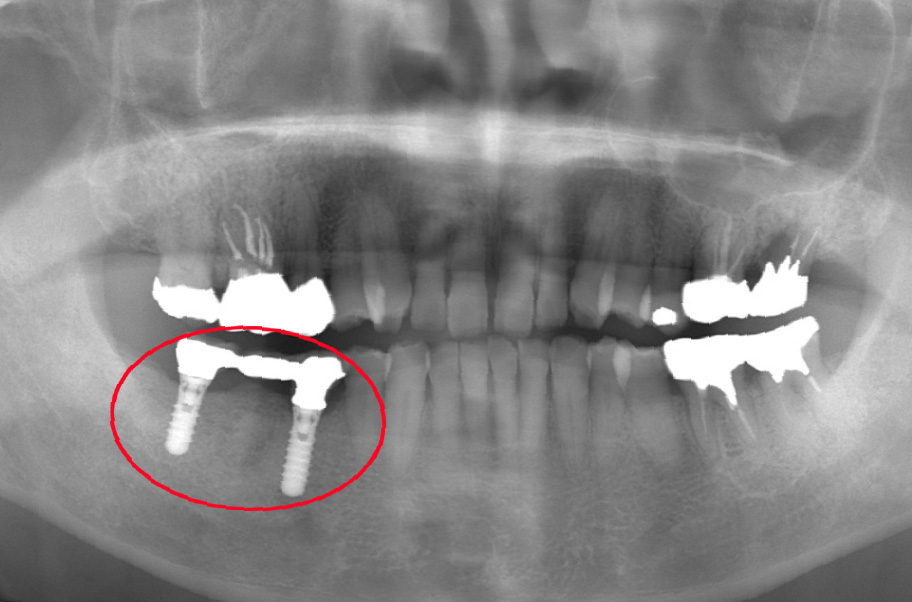

【16年後】2025年4月83歳

それから16年が経ち、現在83歳になられましたが、インプラントの状態は非常に良好です。

そして何より素晴らしいのは、「この16年間、他のご自身の歯を一本も失っていない」という事実です。

「インプラントがしっかりと噛む力を引き受け、支えてくれたおかげで、他のご自身の歯への負担が減った」からこそ、残りの歯が守られたのです。